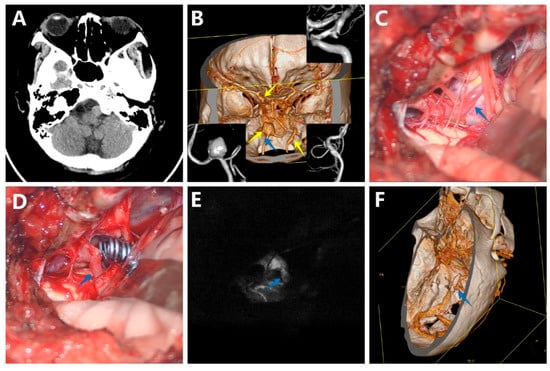

3.5.2. Case 2